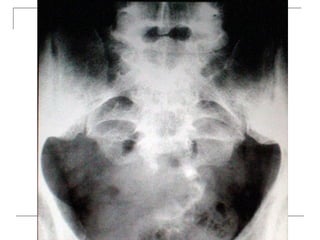

Plain radiograph

   AP

-loss of lumbar lordosis

-reduced disc space

-osteophytes

-deformity

-fracture (increase interpedicular distance)

-osteoporosis

-pedicle disruption

Plain radiograph  AP -loss of lumbar lordosis -reduced disc space -osteophytes -deformity -fracture (increase interpedicular distance) -osteoporosis -pedicle disruption

• 25.

Lateral -fracture/wedging -kyphosis -spondylolisthesis  Oblique -spondylolysis (SCOTTIE DOG)